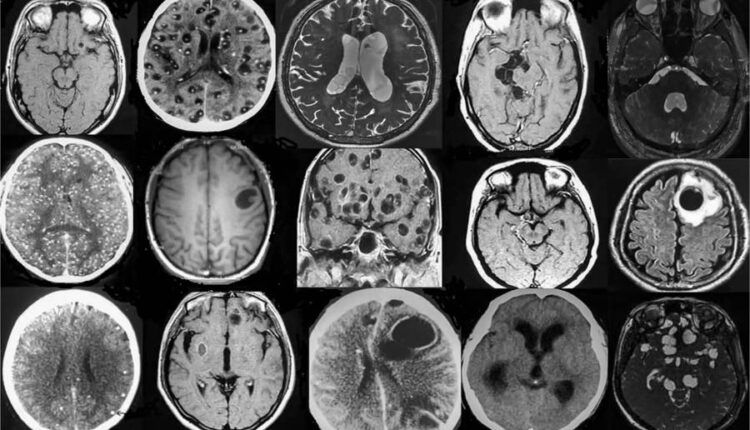

Durante el encuentro a distancia organizado por Sorbonne Université y el Centro de Estudios Mexicanos UNAM-Francia, la neuróloga detalló que el cerebro es el órgano afectado con mayor frecuencia por este padecimiento, aunque su gravedad es variable: “A veces es benigna con pequeños quistes, y otras puede ser muy grave, comprometiendo incluso la vida de los pacientes”.